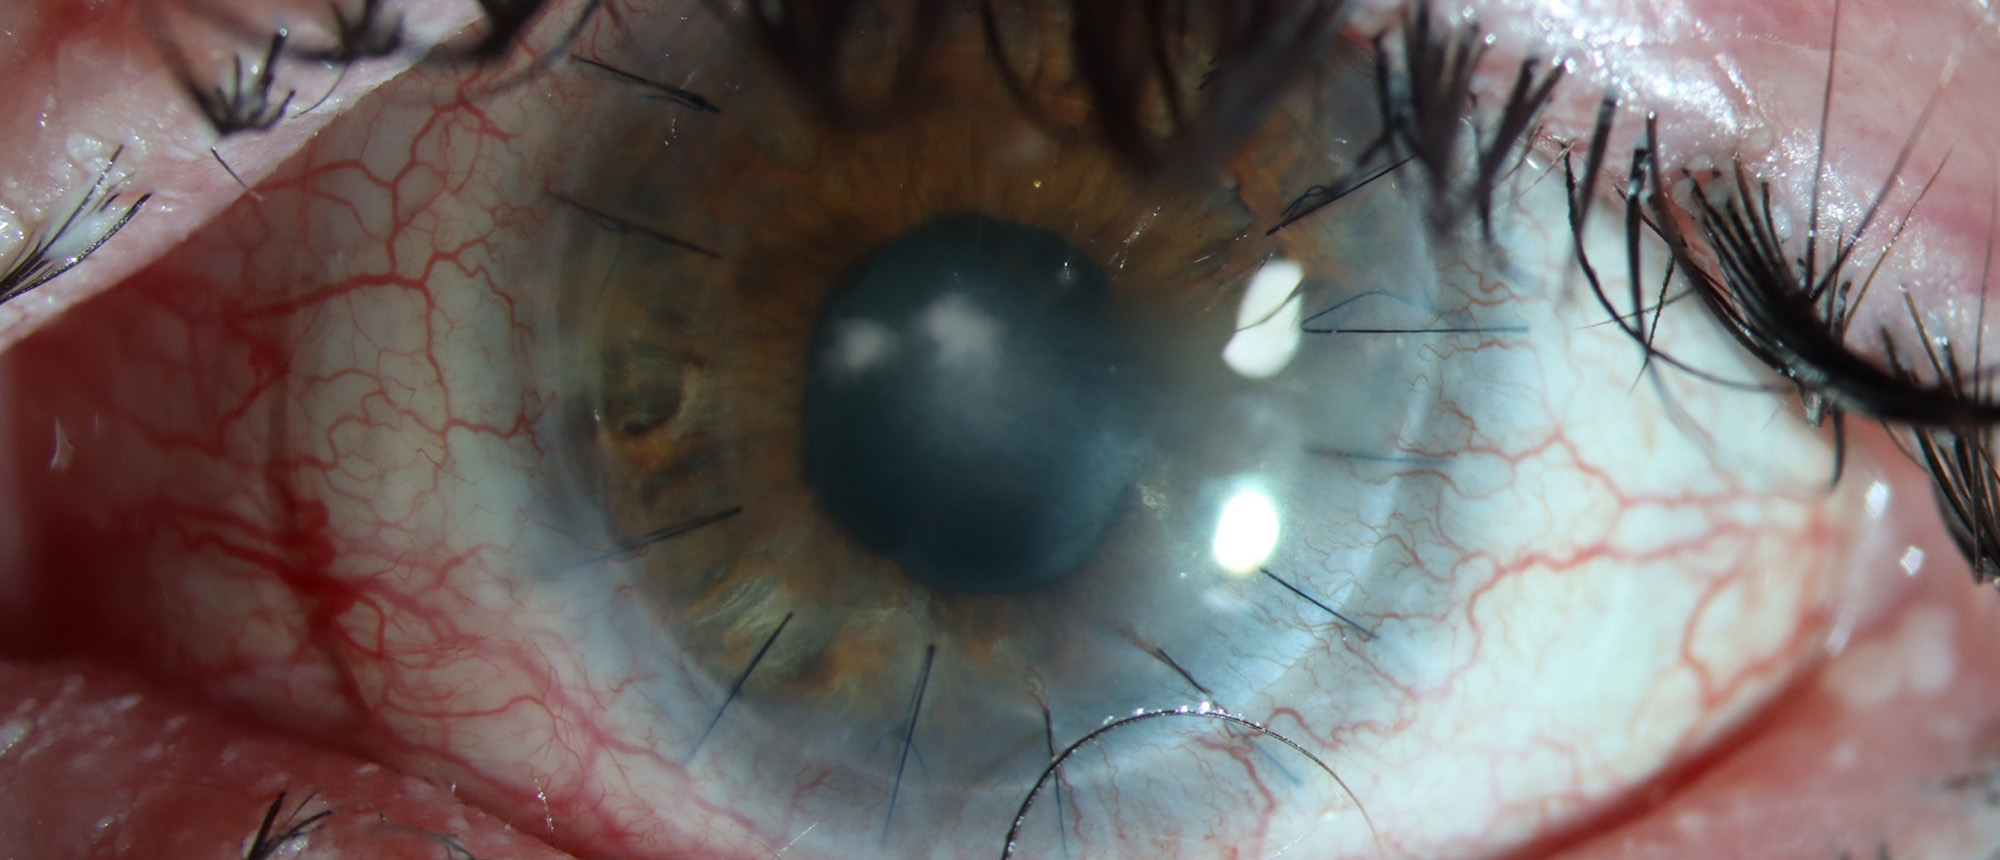

Fuchs Endothelial Corneal Dystrophy

Original Contributor(s): Ellen Koo, MD; Jacob Fondriest, MD

Presenter/Faculty: Koo, Fondriest

A patient with Fuchs' Endothelial corneal dystrophy. Slit lamp photos with retroillumination demonstrate corneal guttate.